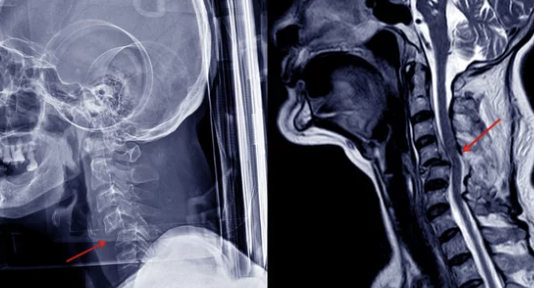

목 디스크는 경추 뼈 사이에 있는 디스크가 탈출하거나 파열되어 신경을 압박하면서 통증을 유발하는 질환입니다.

저는 처음에는 단순한 근육통인 줄 알았는데, 팔까지 저리고 손가락 감각이 둔해지는 증상이 나타나면서 병원을 찾았습니다. MRI 검사 결과 목 디스크 진단을 받았고, 그때부터 본격적인 치료를 시작했죠.